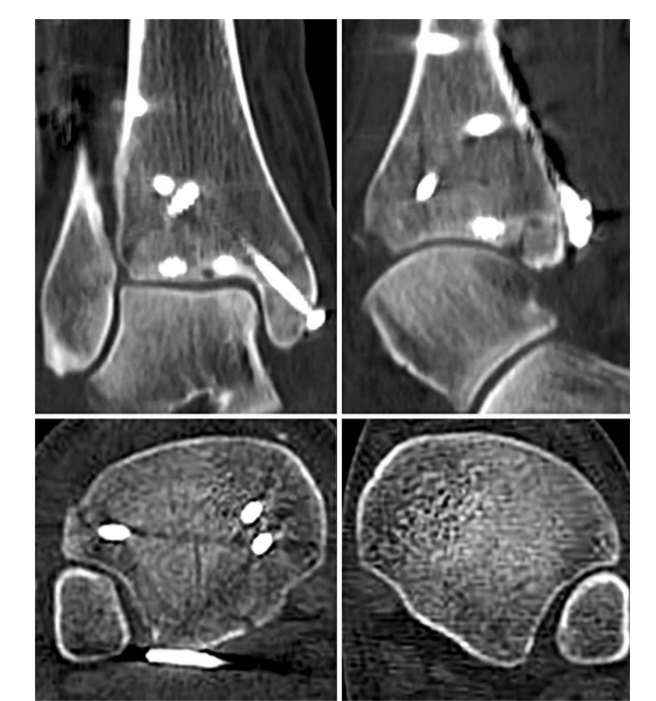

② 四踝骨折典型病例图。

⑧ 复位后典型病例示意图。